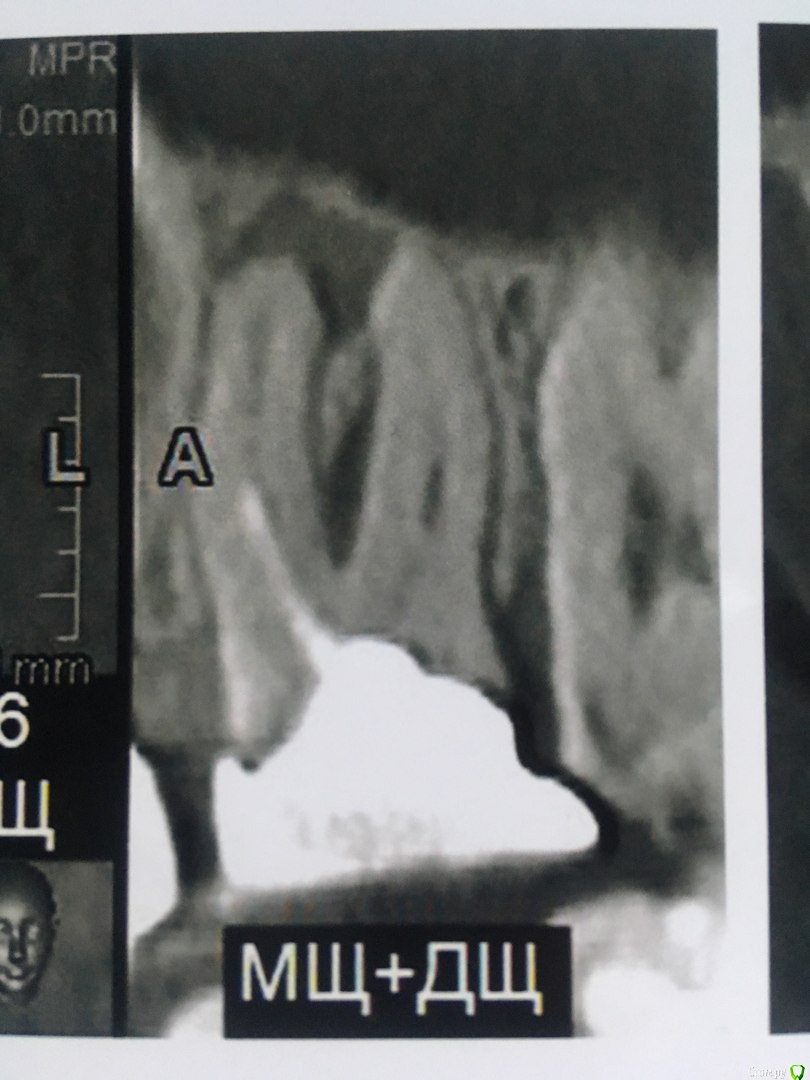

В течении  года от зуба опустилась десна и там проглядывается прозрачно-черный корень и очень быстро на 5 и 4-ки обазовались черные пятна.  Сделала КТ. Теперь стоит вопрос долгое  лечение или удаление.Врач говорит все будет видно при вскрытии. Если лечение то долгое и без гарантий.   Мне кажется от корня там мало что осталось,судя по цвету и по тому как быстро испортились рядом стоящие зубы. Может проще не лечить,установить имплант?

Правда один врач сказал,что то вроде убыли костной ткани и имплант удержать будет не чем,кроме того сужение верхней челюсти, рецессия десны и стирание в пришеечной области из за прикуса. В заключении кт -пародонтопатия легкой степени тяжести.

Добрый вечер!  Благодарю за ответ. Побывала у другого врача. Мнения разошлись. Второй доктор сказал 4,6  удаляем, а верхний 2,6 лечим.Первый же доктор сказал наоборот. Можно спросить еще Ваше мнение по 2,6 и 2,5 зубам?)